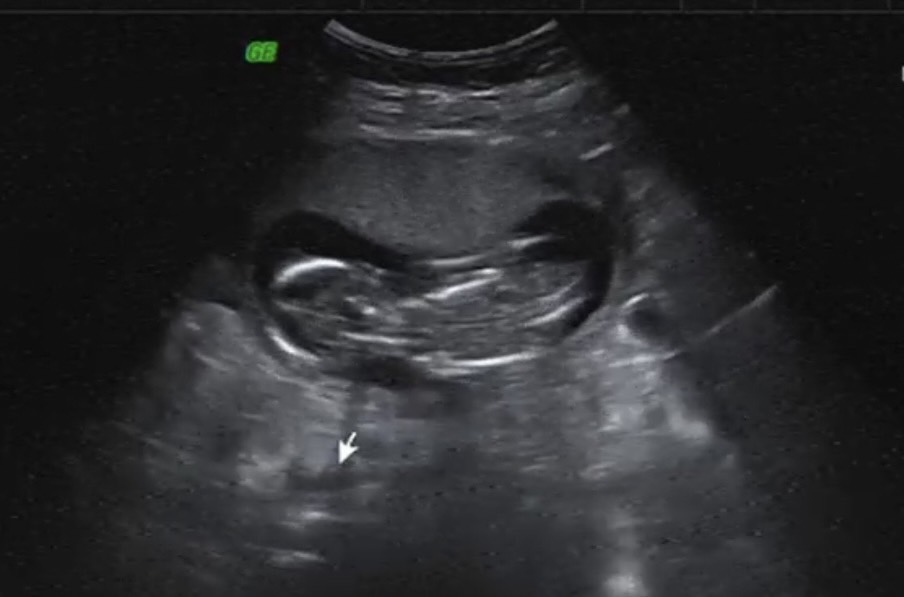

▲ 葉家妤寶寶超音波曝光。(圖:民視)